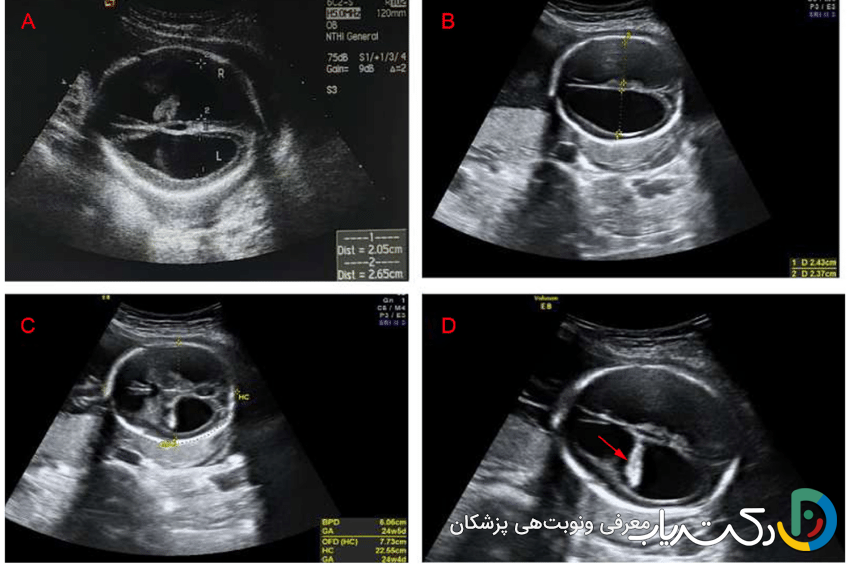

• ونتریکولومگالی: کلیدی‌ترین یافته‌ای که در سونوگرافی شک به هیدروسفالی را برمی‌انگیزد، ونتریکولومگالی یا بزرگ شدن بطن‌های جانبی مغز است. رادیولوژیست عرض دهلیز بطن‌های جانبی را اندازه‌گیری می‌کند.

• اندازه‌گیری طبیعی: کمتر از ۱۰ میلی‌متر.

• ونتریکولومگالی خفیف: بین ۱۰ تا ۱۵ میلی‌متر.

• ونتریکولومگالی شدید: بیشتر از ۱۵ میلی‌متر.

• اهمیت یافته‌ها و علائم مرتبط: تشخیص ونتریکولومگالی همیشه به معنای هیدروسفالی نیست، اما یک زنگ خطر جدی است. متخصص سونوگرافی به دنبال سایر علائم مرتبط نیز می‌گردد، مانند عدم وجود ساختارهای دیگر مغزی (مثل کورپوس کالوزوم) یا ناهنجاری‌های ستون فقرات (مانند اسپاینا بیفیدا). این یافته نیازمند بررسی‌های بیشتر مانند سونوگرافی‌های هدفمند و دقیق‌تر، MRI جنین برای ارزیابی بهتر آناتومی مغز و مشاوره ژنتیک است تا علت زمینه‌ای آن مشخص شود.

• تصاویر حاصل: سونوگرافی جمجمه به وضوح اندازه و شکل بطن‌ها را نشان می‌دهد و می‌تواند وجود خونریزی ، کیست، آسیب به بافت اطراف بطن‌ها یا سایر ناهنجاری‌های بزرگ را مشخص کند.